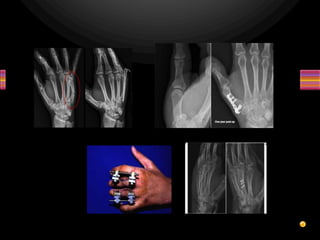

• Kết hợp xương:

– Xuyên đinh

– Vit

– Nẹp

– Bất động ngoài

 Tôn trọng khớp